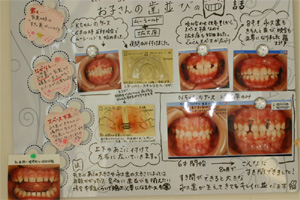

�q���̎����}�E�X�s�[�X�Ŏ��Â���

�c�����`�Љ�l�̎����сA�R���Ɋւ����ʋ����̎��Â���я����̎��i���Ι����j�̎��Â��s���Ă���܂��B

��N��̎��i���������Ι����j�̎��Âł́A�}�E�X�s�[�X�^�̋������u�w���[�V�[���h™�x���g�p���܂��B�A�Q���݂̂̎g�p�Ŏ��Ì��ʂ��グ�邱�Ƃ��o���܂��B

���̃��[�V�[���h™���g�p���邱�Ƃɂ��A���Ι����́A�i�v����������܂ő҂��ƂȂ��A�R�Ύ�����̎��Â��\�ɂȂ�܂����B

�y ���ÑO �z |

�y ���Éߒ� �z |

�y ���� �z |